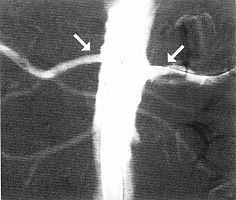

Az erek vizsgálatára alkalmazott eljárás, melynek során azok belső terébe (lumenbe) kontrasztanyagot juttatnak, majd röntgensugárral átvilágítják a kérdéses részt. A kontrasztanyagon nem tudnak áthatolni a sugarak, így ott fekete marad a kép (árnyékot ad). Az ilyen technikával elkészített felvétel neve: angiogram.

Angiográfiának neveznek minden, az ereket ábrázoló, invazív és nem invazív (beavatkozást nem igénylő) eljárást, mint a CT, az ultrahang és az MRI-vizsgálat. Klasszikus értelemben azonban az angiográfia a kontrasztanyag befecskendezéssel jelölt, röntgensugárzás segítségével történő érábrázolás.

Attól függően, hogy artériát, vénát, vagy nyirokeret vizsgálnak, megkülönböztetünk arterio-, flebo- és limfangiográfiát. Az eljárással kimutathatók az ereket érintő legáltalánosabb rendellenességek, mint az érszűkület, vagy érelzáródás, az érfalon található tágulatok (aneurizma), illetve a rendellenes érösszeköttetések (arteriovenosus malformatiok), valamint egy-egy terület fokozott erezettsége, amely rosszindulatú daganatra utalhat.